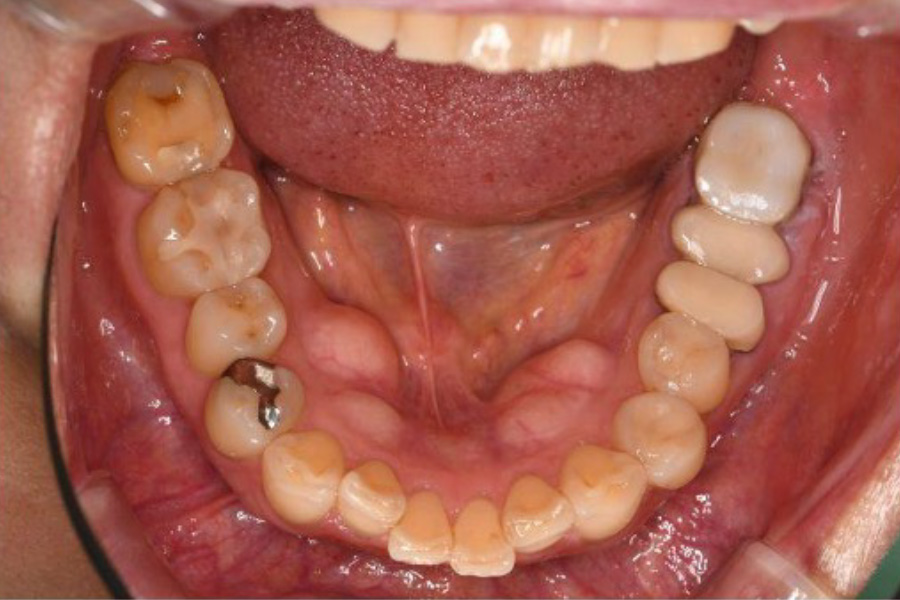

【口腔内写真】下顎咬合面

(噛み合わせの面)の全景

お口の内側(舌側)に見えるボコボコとした突起は「骨隆起」と呼ばれるもので、過酷な噛む力に耐えようとして身体が地盤を厚く補強した、いわば『力のストレス』の顕著な証拠です。

左下奥歯には、破折した根を分割した上で、強固なジルコニアクラウンを装着しています。繰り返された噛み合わせ調整の跡は、いかにこの部位に複雑で強い力が集中していたかを物語っています。

一方の右下奥歯は、激しい摩擦(咬耗)によって歯の表面のエナメル質が消失し、内部の象牙質が広範囲に露出しています。そこにある古い詰め物の周囲には、過度な力による「ヒビ(クラック)」を入り口として、細菌による二次的な虫歯が進行しています。

その他、各所に見られる段差のある不適合な修復物は、細菌の温床となりやすく、お口全体の健康を脅かす構造的なリスクとなっていました。